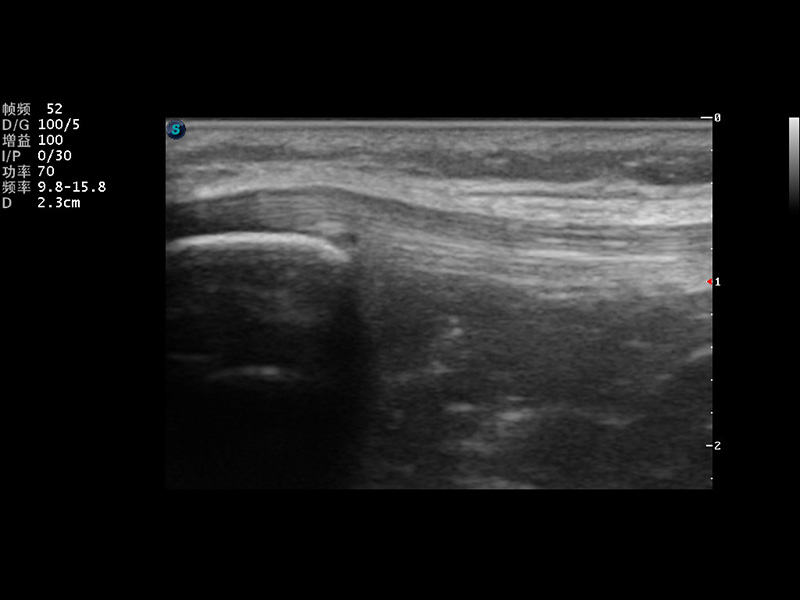

S9便携式彩色多普勒超声诊断仪是美狮贵宾会官网研发的高端便携彩超设备,外观设计新颖、产品性能卓越。S9在便携超声领域采用了突破传统的触摸屏交互设计,并以先进的软件硬件技术和设计理念,为您带来清晰的图像质量、稳定的工作性能和便捷的操作体验。